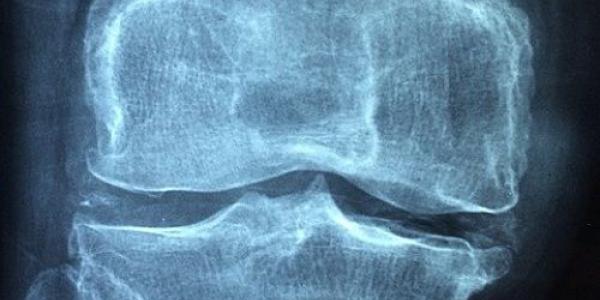

Cada 20 de octubre se celebra el Día Mundial de la Osteoporosis, una enfermedad que afecta a casi tres millones de personas de más de 50 años. Se caracteriza por el deterioro de los huesos. Este día tiene le objetivo de concienciar sobre su diagnóstico y tratamiento.